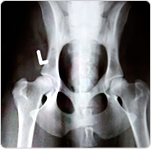

radiología

En nuestras clínicas disponemos de servicio de rayos X para la realización de cualquier tipo de contraste radiográfico para el diagnóstico de su mascota.

El revelado automático nos permite tener la radiografía lista en pocos minutos.